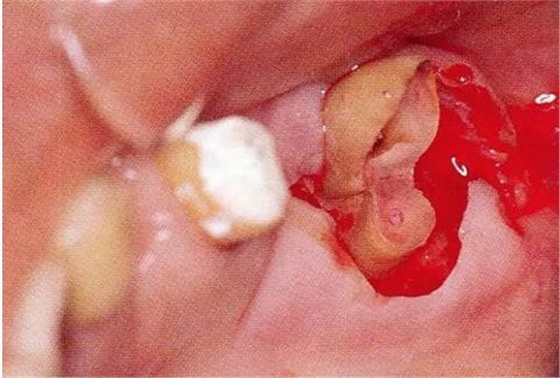

▼圖18-2

圖18-2 拔除近中根的牙齒遠(yuǎn)中面。

▼圖18-3

圖18-3 在其他醫(yī)院進(jìn)行了的修復(fù)處理。拔除了第一磨牙遠(yuǎn)中根的病例。近中根遠(yuǎn)中面殘留著一部分的邊緣。在這種部位很容易滯留牙垢,菌斑的控制會(huì)也很困難。